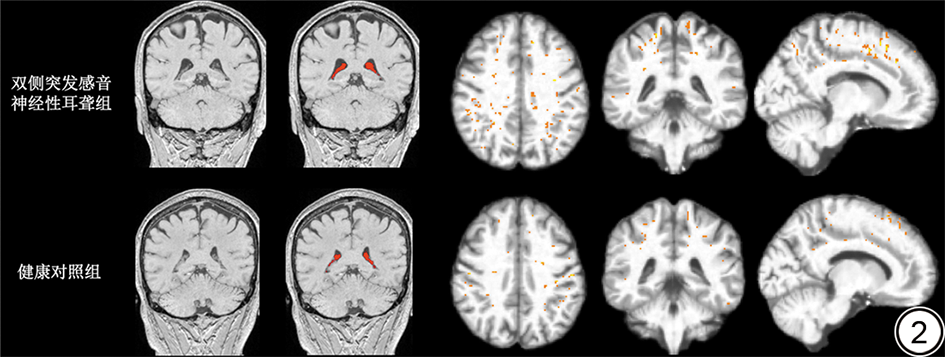

双侧突发感音神经性耳聋患者与健康对照者的颅内总容积差异不具有统计学意义(P>0.05)。双侧突发感音神经性耳聋患者的原始及标准化后的脉络丛体积、血管周围间隙和两侧脑室体积大于健康对照者(P<0.05);而原始及标准化后的第三脑室和第四脑室体积差异不具有统计学学意义(P>0.05)。详见表2。双侧突发感音神经性耳聋患者与健康对照者的脉络丛及血管周围间隙的分割结果对比详见图2

图2  双侧突发感音神经性耳聋患者与健康对照者脉络丛及血管周围间隙分割掩膜对比。红色为脉络丛掩膜;橙色为血管周围间隙掩膜。

Fig. 2  Comparison of choroid plexus and perivascular space segmentation masks in bilateral sudden sensorineural hearing loss patients versus healthy controls. The choroid plexus mask is shown in red, and the perivascular space mask is shown in orange.